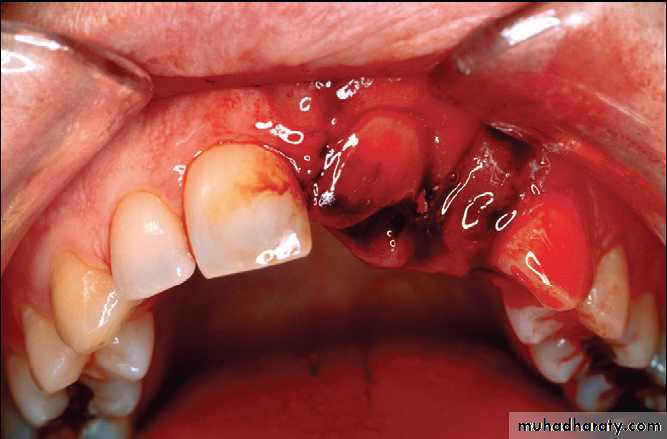

Platally displaced central and lateral incisors in apically mature tooth.

Position of teeth after digital reduction and stabilization with bonded arch wire.- Intrusion